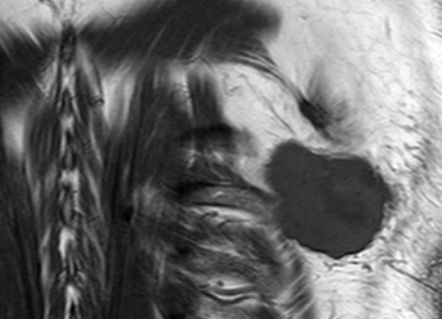

| Rückenmuskulatur | 77-jähriger Patient mit einem pleomorphen Weichteilsarkom über dem Musculus latissimus dorsi ![]() |

Darstellung liquider Anteile nach Biopsie.![]() |